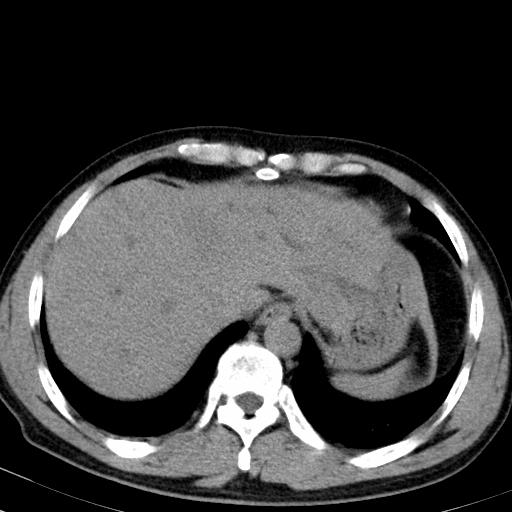

患者上腹部疼痛一月余,伴巩膜黄染;

实事求是的说,强化效果很一般,重点部位应重点观察,但有一点可以明确:肝门部胆管细胞癌。

考虑肝左叶胆管细胞癌侵犯肝门区并肝内胆管及肝总管扩张。

肝左叶肿块清度增强,所在的叶胆管扩张。考虑胆管细胞癌。

考虑肝左叶胆管细胞癌侵犯肝门区并肝内胆管及肝总管扩张、肝门淋巴结肿大。